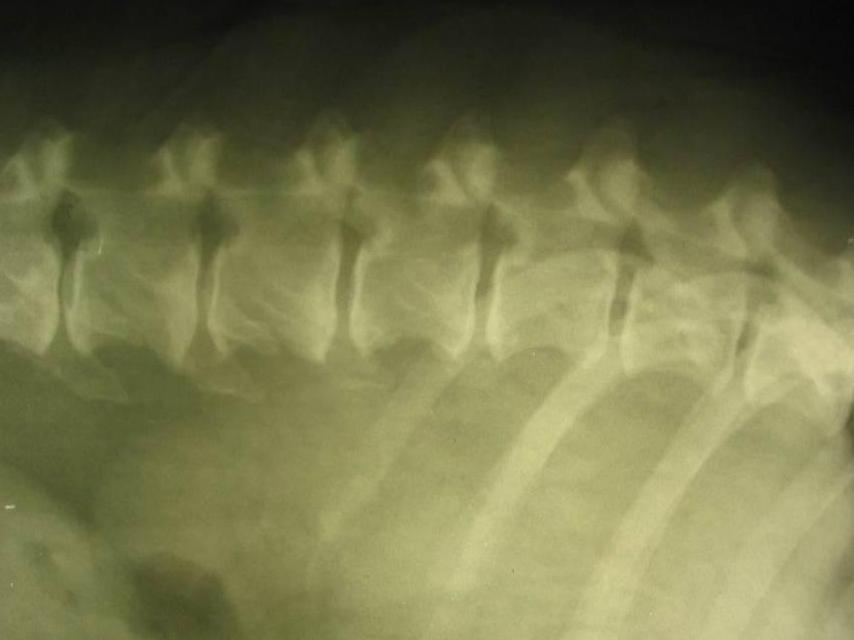

Миелография - это метод рентгенологического исследования, позволяющий наблюдать спинномозговой канал. Он заключается в введении рентгеноконтрастного вещества в подпаутинное пространство. Получаемое с помощью рентгеновских лучей изображение называется миелограммой.

Спинной мозг покрыт твердой, паутинной и мягкой оболочками, удерживается в постоянном положении связками. Все пространства между оболочками и канал заполнены спинномозговой жидкостью (ликвором). При проведении миелографии в подпаутинное простаранство вводят рентгеноконтрастное вещество, затем врач выполняет миелограмму исследуемого участка спинного мозга. Рентгеноконтрастное вещество почти не проводит рентгеновские лучи, поэтому на рентгеновском снимке видна вся твердая оболочка спинного мозга. При наличии патологических изменений, например, опухоли, контрастное вещество в этом месте прекращает свое движение или его ток сужается. В последние годы чаще применяются современные методы исследования, например, компьютерная томография и ядерно-магнитный резонанс, миелография применяется реже.

Рентгеновский снимок